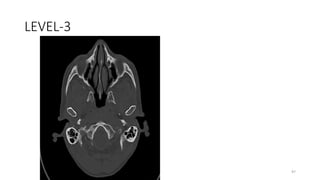

LEVEL-3

20

97

Superior view

MASTOID PROCESS

21

98

Posterior view

OCCIPITAL BONE

22

99

23

OCCIPITOMASTOID SUTURE

24

100

25

PTERYGOMAXILLARY FISSURE

26

101

27

PTERYGOPALATINE FOSSA

Anterior fossa foramina

102

• Foramen cecum